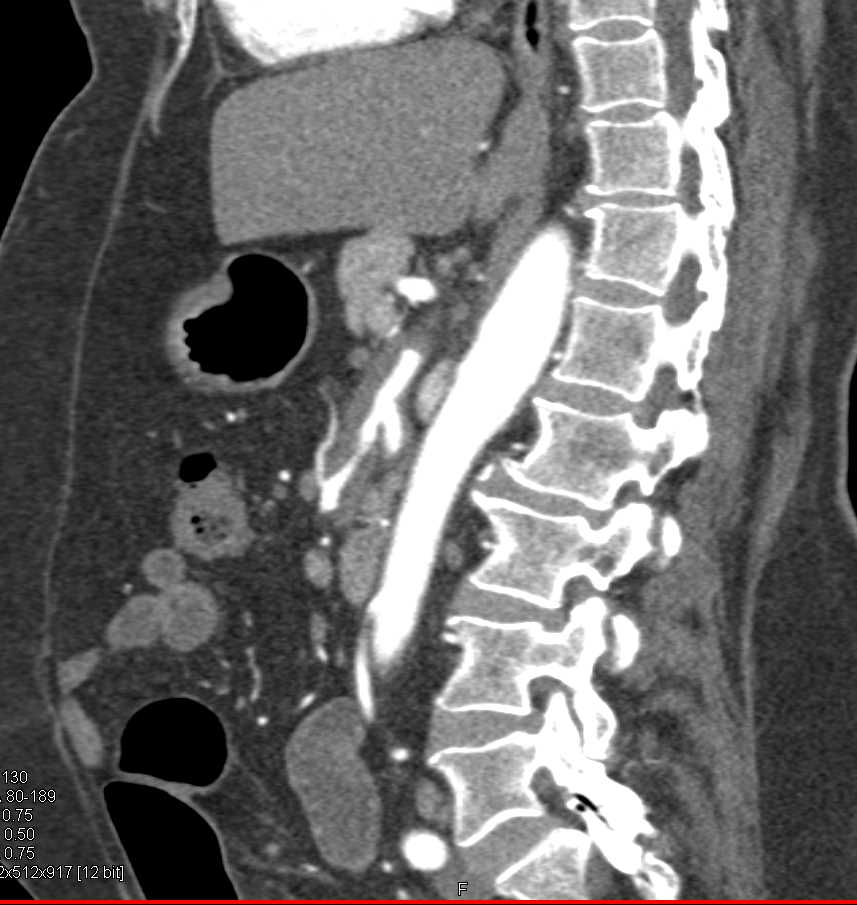

Neuroendocrine Tumor Body of Pancreas